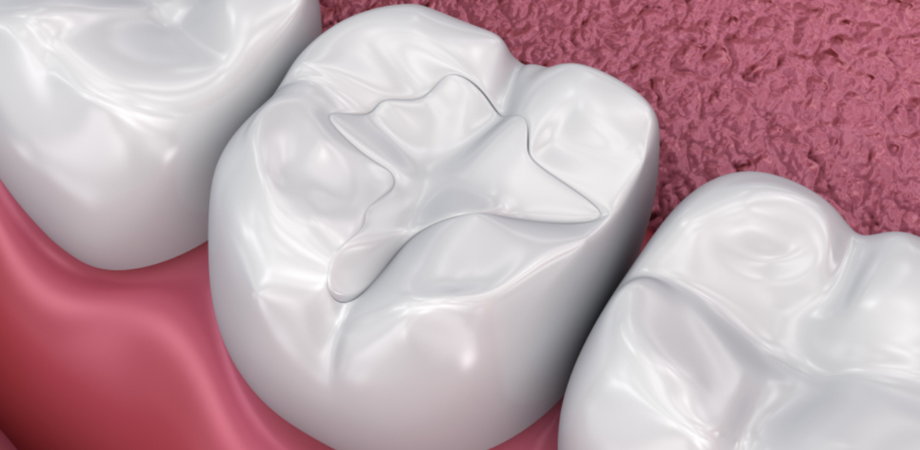

A curetagem pulpar é um procedimento odontológico realizado quando a polpa dentária está inflamada ou infectada. Essa técnica consiste na remoção do tecido infectado ou inflamado da polpa dentária, utilizando instrumentos especializados para limpar e desinfectar o canal radicular.

Após a limpeza, o espaço é preenchido com materiais que previnem novas infecções e selam o dente para evitar que bactérias penetrem novamente.

Esse tratamento é particularmente útil em casos onde a inflamação não afeta toda a extensão da polpa ou quando a endodontia convencional pode não ser indicada. Além disso, a curetagem pulpar pode ser realizada como uma forma de tentar preservar parte da polpa saudável, mantendo assim a vitalidade do dente por mais tempo.

Embora o procedimento seja menos invasivo que uma endodontia completa, ele exige precisão e conhecimento técnico por parte do dentista para garantir que o canal radicular seja completamente limpo e selado, evitando complicações futuras.